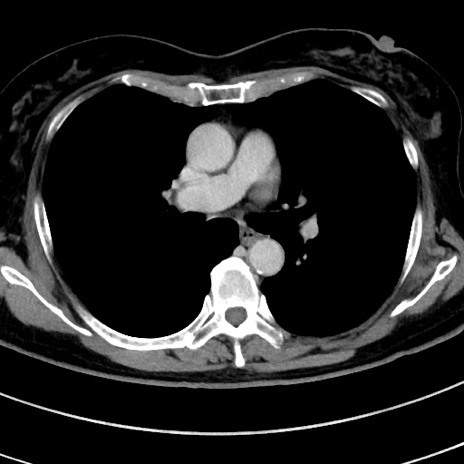

症例9(横断像)

【症例】 60歳代女性

【主訴】むかつき、みぞおちの痛み

【現病歴】3日前よりむかつきがあり、食事がとれない。

【既往歴】糖尿病

【身体所見】発熱なし、心窩部圧痛軽度あるも、腹膜刺激症状なし。

【データ】WBC 7400、CRP 1.92